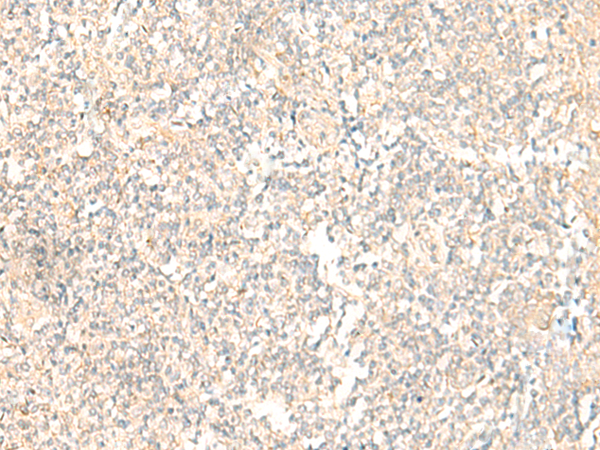

分类: 科研抗体货号: P11069别名: LKS; EPND; FESD; NR2A; GluN2A; NMDAR2A应用: IHC反应种属: Human, Mouse, Rat